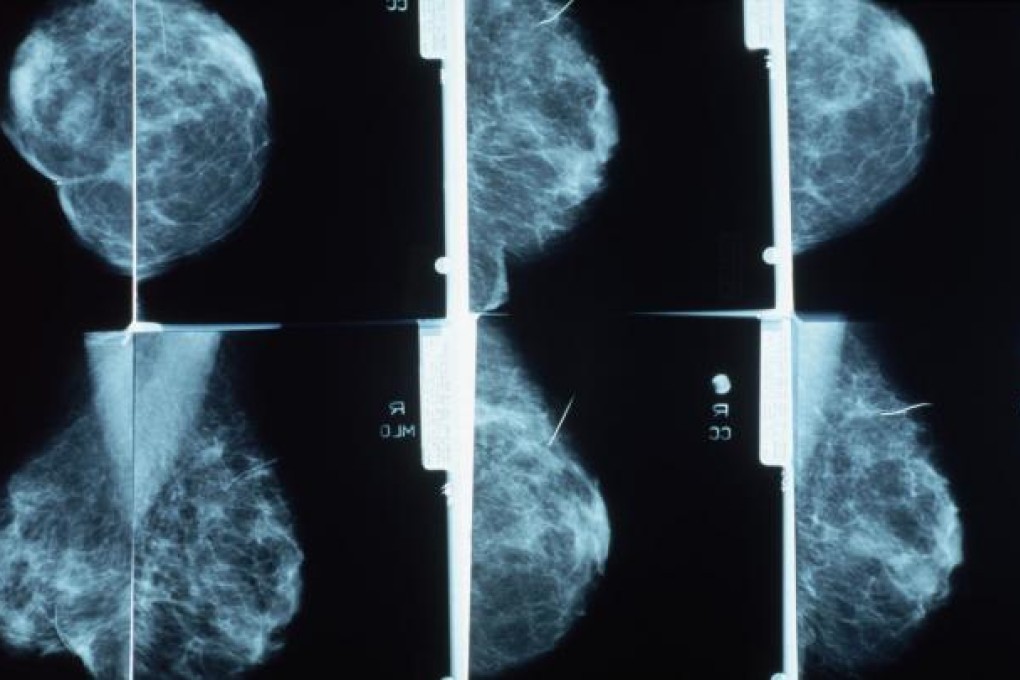

Breast cancer screening for women over 50 saves lives, an independent panel in Britain has concluded, confirming findings in US and other studies.

In Britain, mammograms are usually offered to women aged 50 to 70 every three years as part of the state-funded breast cancer screening programme.

Scientists said the British programme saves about 1,300 women every year from dying of breast cancer, while about 4,000 women are overdiagnosed. By that term, experts mean women treated for cancers that grow too slowly to ever put their lives at risk. This is different from another screening problem: false alarms, which occur when suspicious mammograms lead to biopsies and follow-up tests to rule out cancers that were not present. The study did not look at the false alarm rate.